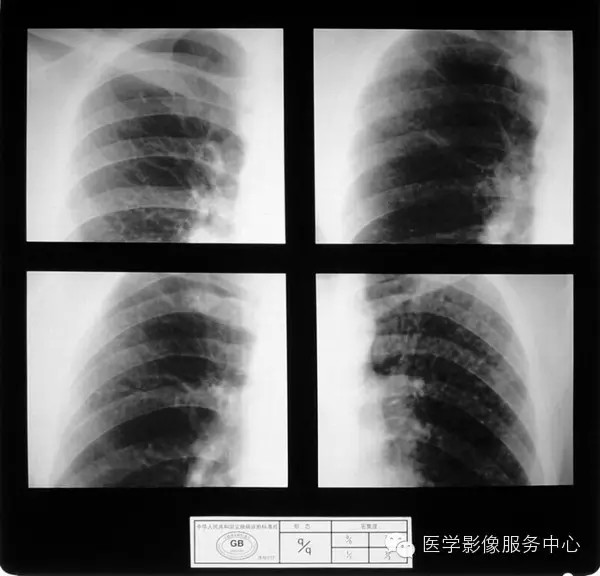

4.4 三期尘肺(Ⅲ)

a)Ⅲ:有大阴影出现,其长径不小于20mm,短径不小于10mm。

b)Ⅲ :单个大阴影的面积或多个大阴影面积的总和超过右上肺区面积者。